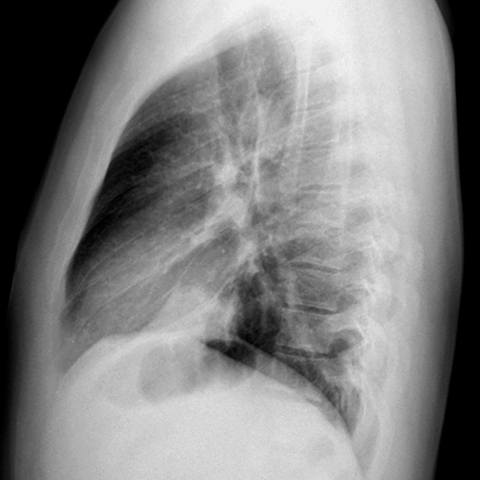

Silhouette Sign, LLL Pneumonia (Lateral CXR) [2 of 2]